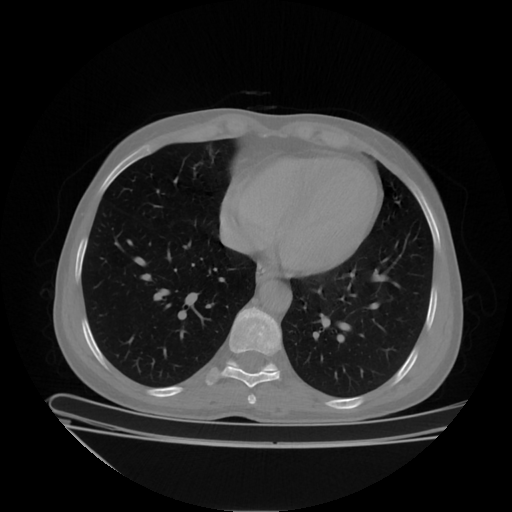

Generated VENOUS CT scan (A→B translation)

Full window (WL 1023.5, WW 4095 β†’ Low βˆ’1024, High +3071)

Lung window (WL -600, WW 1500 β†’ Low βˆ’1350, High +150)

Mediastinum window (WL 40, WW 400 β†’ Low βˆ’160, High +240)